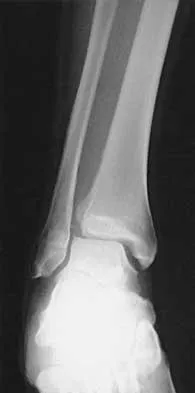

Prepare for AAOS, ABOS, and OITE exams with Set 4 Foot & Ankle MCQs. Covers high-yield topics like ankle frac…